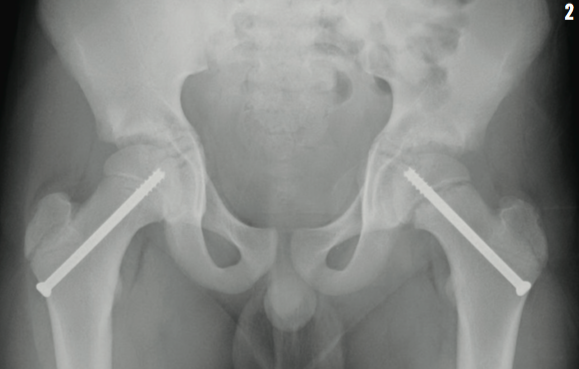

Hip pain in children can indicate a variety of possible diagnoses (Table).1-3 In our patient, the AP radiograph of the hip showed a Type 1 Salter-Harris fracture, or slipped capital femoral epiphysis (SCFE), of the left physis. The boy underwent surgical pinning of the affected and unaffected hips the next day (Figure 2).

The aim of management is to prevent further slipping and complications such as avascular necrosis and osteoarthritis, and this is usually achieved by percutaneous pinning.5 Our patient underwent prophylactic pinning of the normal hip.11 This procedure carries some risk of avascular necrosis, chondrolysis, and fracture, but approximately 24% of untreated patients can develop a contralateral SCFE within 18 months.12 Factors such as age, obesity, follow-up ability, and contralateral radiography findings support preventative intervention.13 After surgery, the patient resumed full weight bearing and returned to football after 6 months.